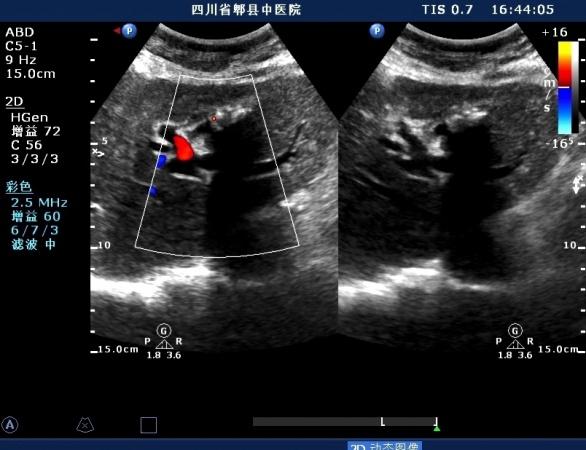

超声如图:胆总管及肝内胆管扩张,呈“平行管征”,胆总管胰腺段可见疏松强回声团堆积,后方可见淡淡声影,左肝外叶胆管内亦可见数个强回声团堆积,后方伴声影。 肝脏及胆总管

胆总管胰腺段结石